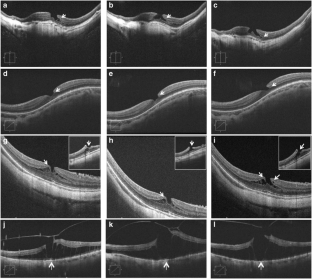

Fig. 1